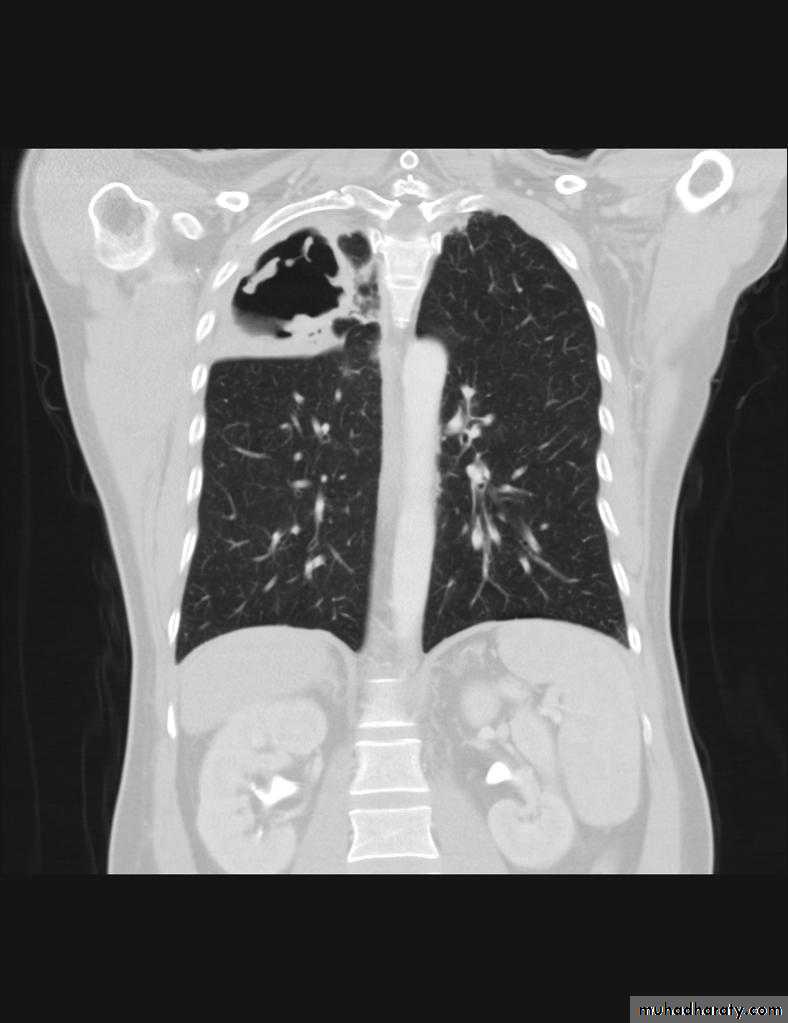

TB lung abscess

Aspergilloma

67. upper apical TB cavity68. Aspergilloma